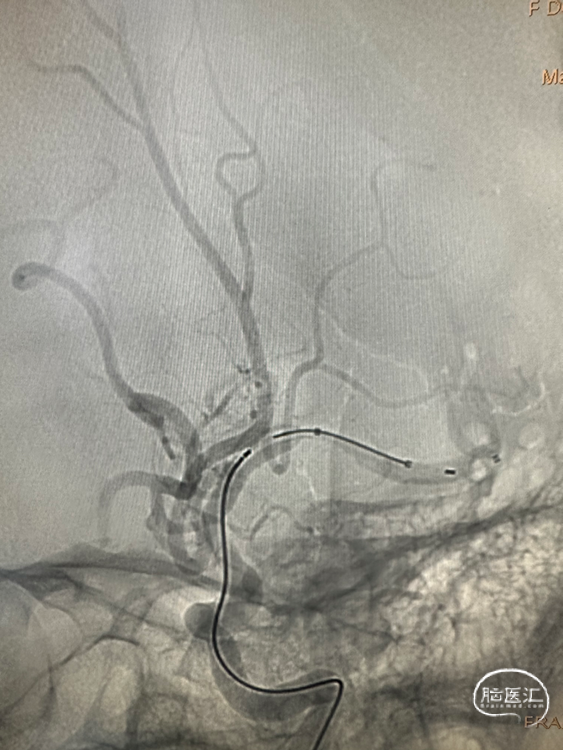

21系列 Fastunnel®输送型球囊扩张导管 2.5mm*10mm

0.014inch 微导丝

4.0*23mm 自膨式闭环支架

Fastunnel®输送型球囊扩张导管 2.5mm*10mm沿微导丝输送到位,充盈球囊扩张狭窄病变。

4.0*23mm 自膨式闭环支架沿21系列 Fastunnel®输送型球囊扩张导管输送到位造影。